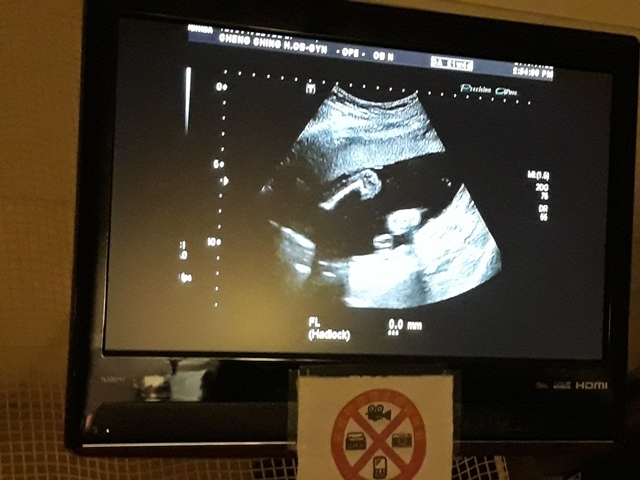

進到超音波室後,發現幫小純照超音波的就是關醫師(小純原本以為會是超音波技術員,照完才會有醫師來,結果是關醫師從頭照到尾)。關醫師一項一項的幫小飛做檢查,雖然是高層次的超音波,比平常的產檢還仔細,但是很多東西我和小純都看不太出來,但是手、腳的指頭和脊椎都很清楚。

檢查到外生殖器時,關醫師說『平平的』是女生,我和小純聽了都感到很訝異,上一次的產檢,關醫師不是說看到『凸凸的』是個男生,月中羊膜穿刺的報告出來之後,小純也有詢問打電話給他的人,也說是男生,怎麼性別翻盤了,小純跟關醫師說,羊膜穿刺的報告說是男的,關醫師說,既然羊膜穿刺的報告是男的,那就是男的沒錯,以羊膜穿刺的報告為準,超音波也有可能會因為角度的問題而誤判,後來關醫師照到小飛把腳打開的樣子,確定是男的。

今天的高層次超音波照下來,小飛還蠻健康的,唯獨FL(大腿骨的長度)的成長,比目前實際的天數(21週又5天)還小(超音波照出來是20週又6天),不過還在正常值內,小純聽到這個消息心情有些Blue,問關醫師多喝牛奶能不能改善,關醫師卻叫小純不要喝太多牛奶:「牛奶喝多了,會有牛脾氣。」關醫師也不只一次的表示,希望孕婦不要吃太多,吃太多會讓小寶寶變大,這樣不利於生產,至於FL成長比較慢的事,關醫師說,孩子出生再補給足夠的營養或者運動即可。